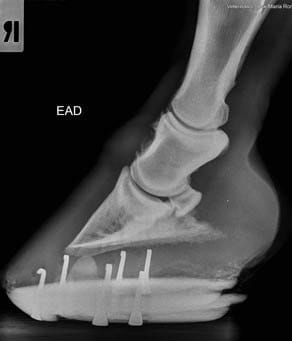

- Cuidados del casco y herrajes ortopédicos

- Medidas e imagen 3D para evaluación del pie equino

- Imagen hibrida. Diagnóstico v herrado